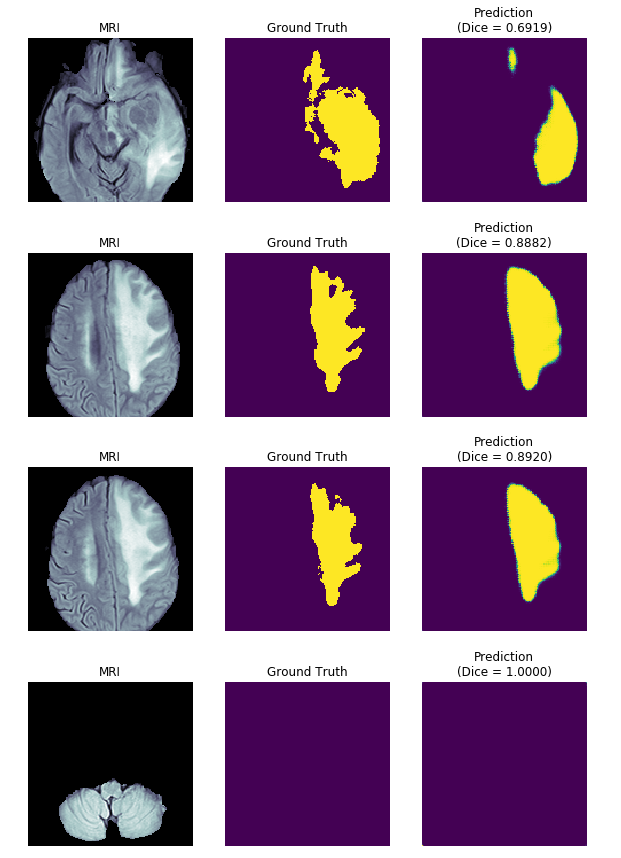

Một số kết quả

Đánh giá model

Về mặt đánh giá, trong bài toán này chúng ta sử dụng hệ số Dice coefficient (số liệu chuẩn cho bộ dữ liệu BraTS được sử dụng trong nghiên cứu). Dice coefficient được sử dụng để so sáng độ tương đồng giữa 2 mẫu. Ví dụ, với 2 tập X, Y thì dice sẽ được tính theo công thức:

Mục tiêu của bài toán là xác định hình dạng, vị trí của khối u não bên trong các hình ảnh 2D hoặc 3D chụp cộng hưởng từ (MRI), từ đó dễ dàng cho việc chuẩn đoán bệnh và lập kế hoạch điều trị.